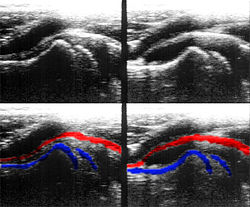

Die Aussagekraft der Sonografie kann erheblich durch die Anwendung des Doppler-Effekts erhöht werden. Man unterscheidet eindimensionale Verfahren (Pulsed-Wave-Doppler, Continuous-Wave-Doppler, auch als D-mode bezeichnet) von zweidimensionalen, farbkodierten Anwendungen (Farbdoppler – F-mode). Die Kombination B-Bild mit Pulsed-Wave-Doppler (PW-Doppler) nennt man auch Duplex.[4]

Doppler-Verfahren werden benutzt zur Bestimmung von Blutfluss-Geschwindigkeiten, zur Entdeckung und Beurteilung von Herz(klappen)fehlern, Verengungen (Stenosen), Verschlüssen oder Kurzschlussverbindungen (Shunts).

Bei der farbkodierten Doppler-Sonografie wird für einen großen Bereich eines konventionellen Ultraschallbildes (Color-Window) die örtliche Doppler-Frequenz (= mittlere Flussgeschwindigkeit) und deren Schwankungsbreite bestimmt. Damit möchte man die Turbulenz der Strömung abschätzen. Aufgrund der statistischen Bewegungen der Streuteilchen ist die Schwankungsbreite der Fließgeschwindigkeit jedoch stets größer als die Turbulenz. Das Ergebnis wird in Falschfarben auf dem B-Bild überlagert, also in Farbtönen von rot und blau für verschiedene Blutgeschwindigkeit und grün für Turbulenz. Hierbei steht üblicherweise die Farbe Rot für Bewegung auf den Schallkopf zu, während mit blauen Farbtönen Flüsse weg von der Sonde codiert werden. Bereiche der Geschwindigkeit 0 werden durch die Elektronik unterdrückt.

Farb-Doppler und PW-Doppler. Innerhalb der Stenose ist wegen der hohen Flussgeschwindigkeit und des resultierenden Alias-Effekts die Geschwindigkeit in Blau kodiert. -